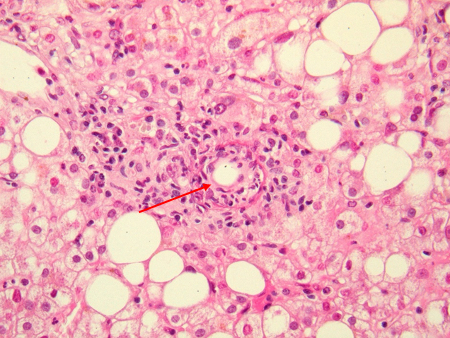

Liver 'doughnut granuloma' characteristic of acute Coxiella burnetii hepatitis. Note the specific granuloma morphology as a doughnut. No bacteria may be seen in this granuloma

Hubert Lepidi, Institut Hospitalo-Universitaire Méditerranée Infection